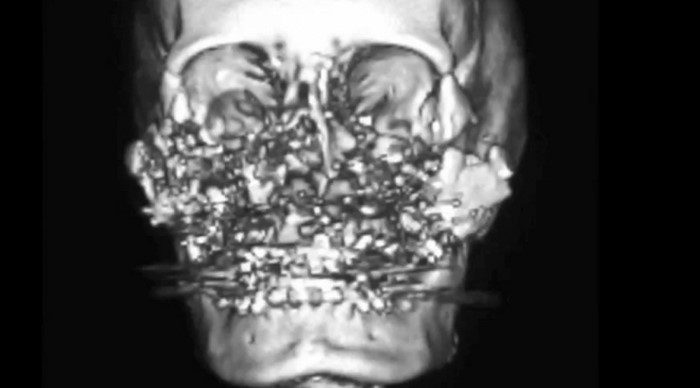

Por sus despiadados crímenes, el bastardo recibió siete años de privación de libertad. A continuación, podrás apreciar cómo quedó el cráneo de Connie luego del salvaje acto. ¡El mero hecho de que la pobre mujer haya sobrevivido es un milagro!

La cara de Connie quedó totalmente desfigurada, semejante a una máscara de una película de terror. El disparo la privó de su nariz, sus ojos, y casi todos sus dientes. Sin embargo, a pesar de esto, la mujer continuó visitando a su marido en la cárcel.